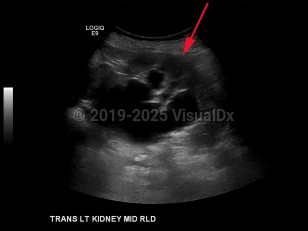

Hydronephrosis in Adult

Nephrolithiasis, prostatic hypertrophy or carcinoma, and retroperitoneal or pelvic neoplasms are the most common causes of hydronephrosis in adults. In children, hydronephrosis is most often secondary to an anatomic abnormality such as posterior urethral valves, vesicoureteral reflux, or ureteropelvic junction (UPJ) obstruction. Bilateral hydronephrosis is most often secondary to bladder tumors that obstruct the outflow of urine. In women, this can be caused by uterine, cervical, or ovarian cancer. Congenital anomalies account for a higher incidence of hydronephrosis in children compared to adults.

The Society for Fetal Urology has developed a grading system for severity of hydronephrosis. Grades range from 0-4; grade 0 is the most mild with no renal pelvis dilation, and grade 4 is the most severe and is characterized by dilation of the renal pelvis and calyces and thinning of the renal parenchyma.

Patients with isolated hydronephrosis are typically pain free; the presence of pain is usually in the setting of stones, acute bladder distension, or infection. Upper ureteral or renal pelvic lesions typically cause flank pain, whereas lower ureteral obstruction causes pain that radiates to the ipsilateral testicle or labia. Other presenting symptoms include hypertension, change in urine output, hematuria, or new creatinine elevation on routine laboratory studies.